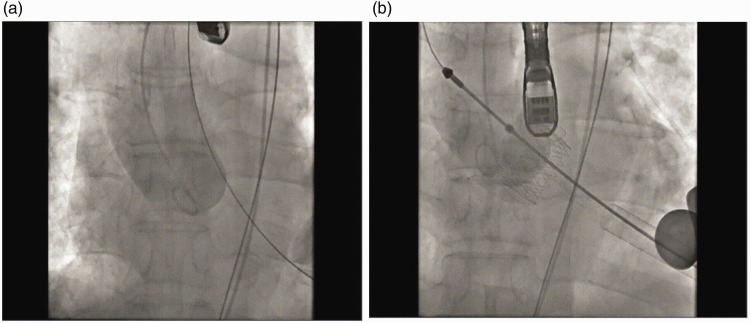

This case report details the successful use of JenaValve for transcatheter aortic valve implantation in a male patient in his early 50s with severe aortic regurgitation. The patient had multiple comorbidities, including chronic kidney disease and heart failure, increasing the risk of surgical intervention. JenaValve, a second-generation device with unique positioning and anchoring mechanisms, was deployed successfully, resulting in immediate improvements in cardiac function without significant regurgitation or paravalvular leakage. This case highlights the potential of transcatheter aortic valve implantation as a viable alternative to surgical aortic valve replacement in patients with severe aortic regurgitation, emphasizing the importance of technological advancements and a multidisciplinary approach in managing complex cardiovascular cases. Long-term follow-up is essential to assess the durability of the implanted valve and the patient's overall prognosis.